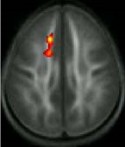

Following the instruction, there were no differences between the poor and average readers with respect to the quality of their white matter. Source: Timothy Keller, Ph.D.; Marcel Just, Ph.D.

At the outset of the study, poor readers showed lower quality white matter than average readers in a brain region called the anterior left centrum semiovale. Six months later, at the completion of the intensive training, the poor readers showed significant increases in the quality of this region. Children who did not receive the training did not show this increase, suggesting that the changes seen in the remedial training group were not due to natural maturation of the brain.

The area where the white matter quality increased (red/yellow area) among poor readers who received the remedial reading instruction. Source: Timothy Keller, Ph.D.; Marcel Just, Ph.D.